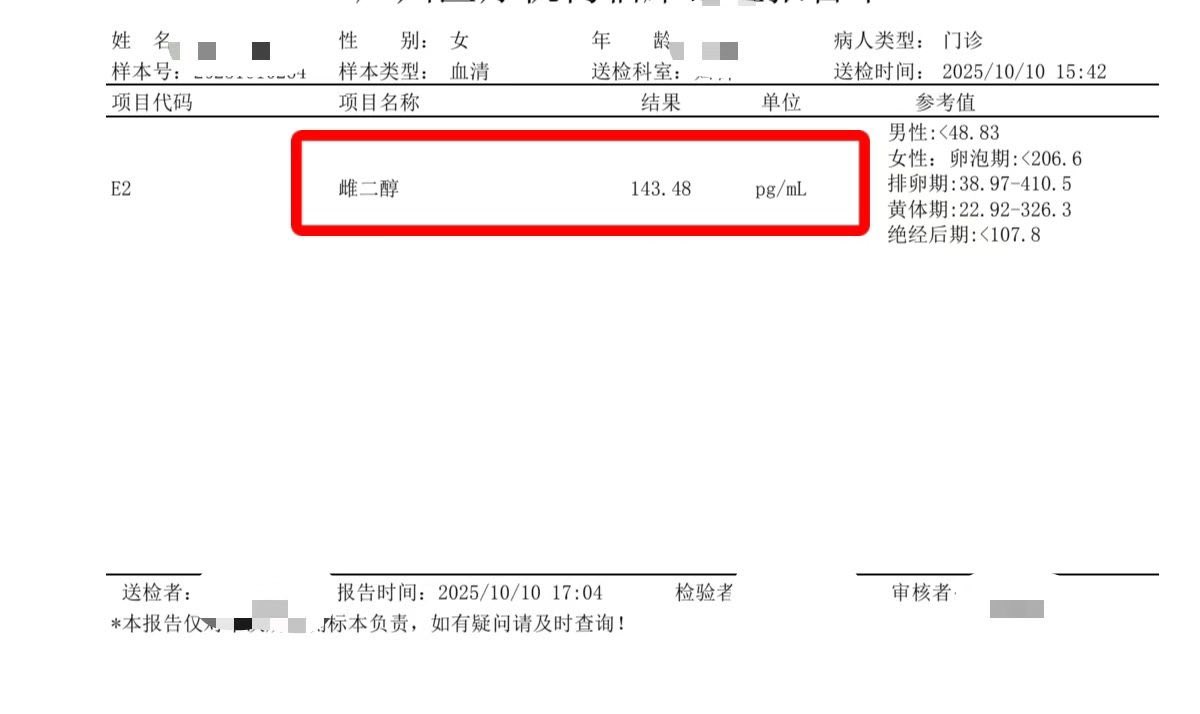

![代孕.HIV.洗精.国内代孕机构 (@wangjb168) on Twitter photo [喜讯]

#男宝 小勇士在护士姐姐的巧手下,裹着暖暖的小抱枕,像在妈妈肚子里一样睡得香甜又踏实~🌙💤 几天后就能回家啦,期待开启“奶爸奶妈”副本,感恩所有朋友对我们信任与支持,使命已完成,愿幸福安康!❤️ 咨询微信:a18025307951

#HIV生子 #三代代孕 #包成功代孕 #洗精代孕 #三代包成功 #广州代孕 [喜讯]

#男宝 小勇士在护士姐姐的巧手下,裹着暖暖的小抱枕,像在妈妈肚子里一样睡得香甜又踏实~🌙💤 几天后就能回家啦,期待开启“奶爸奶妈”副本,感恩所有朋友对我们信任与支持,使命已完成,愿幸福安康!❤️ 咨询微信:a18025307951

#HIV生子 #三代代孕 #包成功代孕 #洗精代孕 #三代包成功 #广州代孕](https://pbs.twimg.com/media/GxpzuEEa0AA2JPY.jpg)